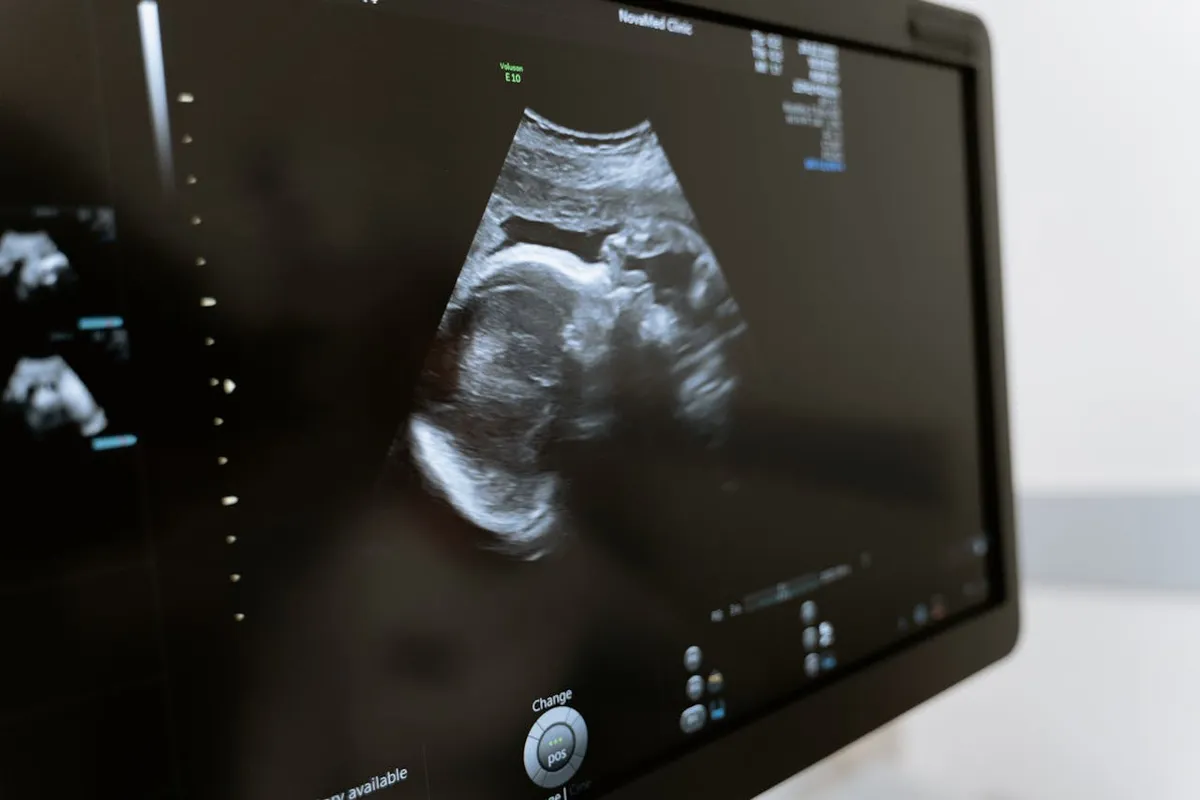

Kizzi Woodman egy londoni nő, akinek első terhességét a remény és izgalom töltötte meg. Három különböző magánklinikán is járt ultrahangvizsgálaton, és minden alkalommal azt mondták neki: a babája egészséges, rendben fejlődik. A klinika megnyugtató visszajelzései után Kizzi végre úgy érezte, hátradőlhet.

De amikor elérkezett a 12 hetes rutinvizsgálat, már az első pillanatban látszott, hogy valami nincs rendben. A szakemberek azonnal jelezték: a magzat belső szervei a testen kívül fejlődtek, súlyos rendellenességek alakultak ki, amelyekkel a baba nem volt életképes.

A nő teljes sokkban hallgatta az orvosi magyarázatot, főként azért, mert az előző három vizsgálat mindent rendben mutatott. A tragédia ráirányította a figyelmet a magánklinikák működésére. A brit Radiográfusok Társasága arra figyelmeztetett, hogy a nem megfelelően képzett személyek súlyos tévedéseket okozhatnak, amelyek veszélybe sodorhatják a kismamákat. Ma az Egyesült Királyságban ugyanis nem kötelező, hogy magzati ultrahangot csak képzett szonográfus végezzen. Kizzi szerint ez a szabályozatlanság vezethetett ahhoz, hogy három vizsgálat sem ismerte fel a rendellenességet.